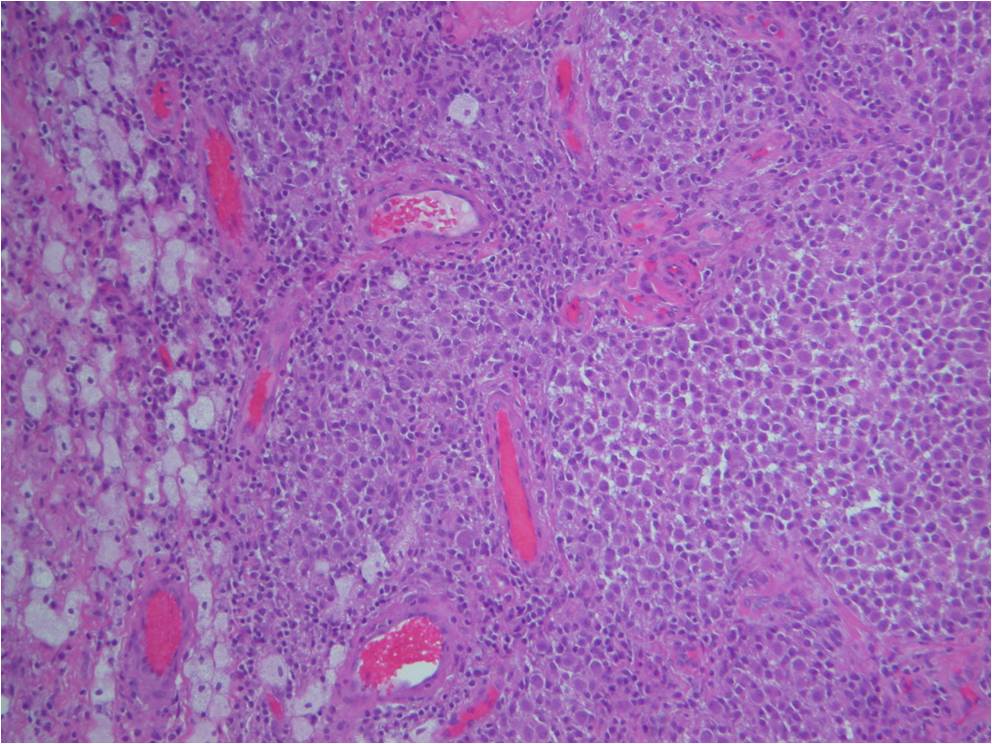

Microscopic

• Dense fibrous tissue divides tumor

• Gives nodular appearance

• Cells

• Small, round to oblong, often reniform or clefted nuclei

• Sometimes prominent nucleoli

• Oblong

• Frequently blend with spindled forms

• Variable numbers of giant cells

• Similar type of nuclei

• Usually contain 8-10 nuclei

• Xanthoma cells

• Sparse mitotic figures

• Low mitotic activity (3 to 5 mitosis x 10 HPF)

• Rarely necrosis is seen

Fig. 7-10: Microscopic pathology. Abundant small hystiocyte-like cells, numerous giant cells and xanthoma cells. In higher magnification images some foamy histiocytes are visible. No mitotic activity is present. Hemosidering deposition is common.